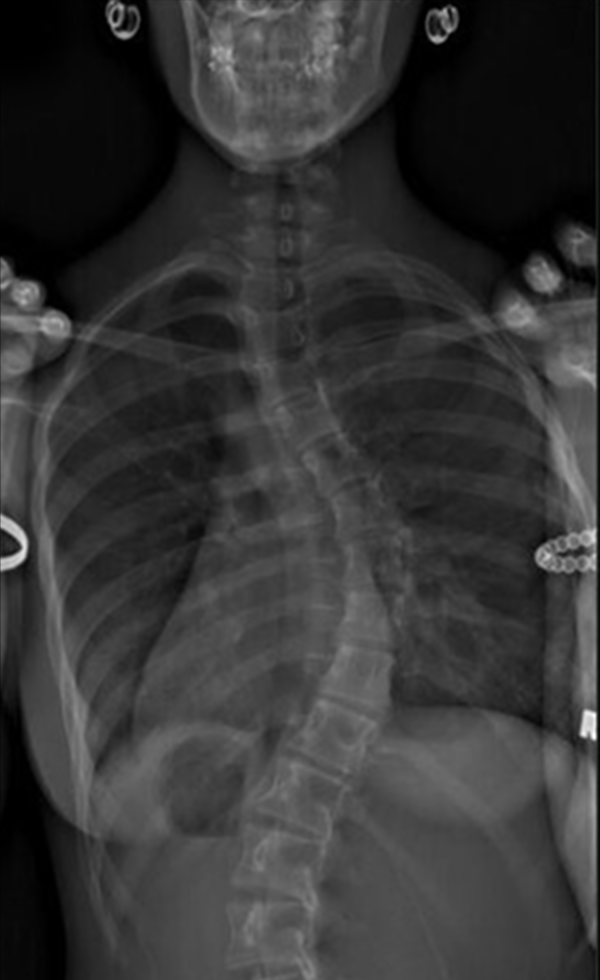

Gallery : Before - After